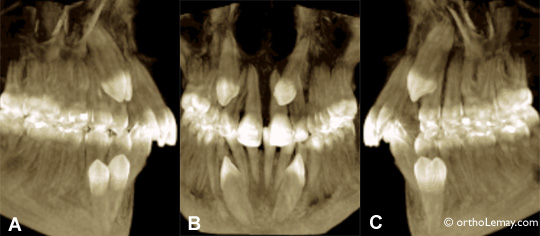

tecno à la rescousse 3

Images extraites d’une tomodensitométrie volumique à faisceau conique chez un jeune adolescent de 17 ans ayant ses 4 canines incluses. (A) Côté droit, (B) centre, (C) côté gauche. La vidéo ci-contre permet d’apprécier la complexité des malpositions de ces dents incluses. On peut voir que la canine supérieure droite cause une légère résorption de la racine de la latérale (voir flèche en mouvement).